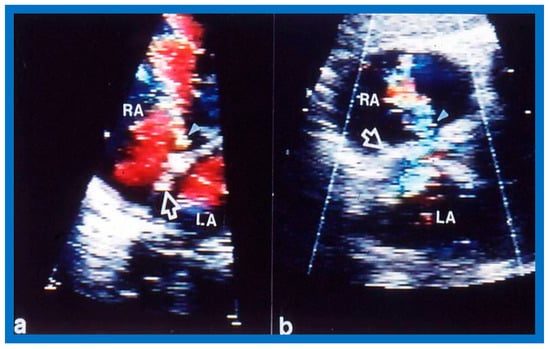

2. Diagnosis